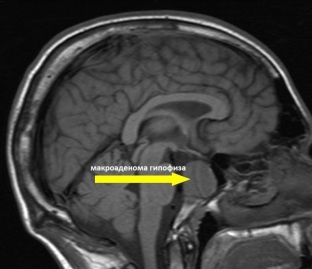

To determine the cause of pathological hyperprolactinemia in women, instrumental diagnostic methods are used, which can determine, first of all, the anatomical cause of the pathology. X-ray examination of the skull may reveal changes in the sella turcica, indicating a neoplasm in the pituitary gland. The pathology is indicated by an increase or expansion of the Turkish saddle, signs of its sclerosis or violation of the integrity of the contours of the entrance to the saddle. Such changes are most characteristic of pituitary macroadenoma. An important role in the diagnosis is played by computed tomography and magnetic resonance imaging, since they can be used to obtain maximum information about the nature, size and localization of the formation.